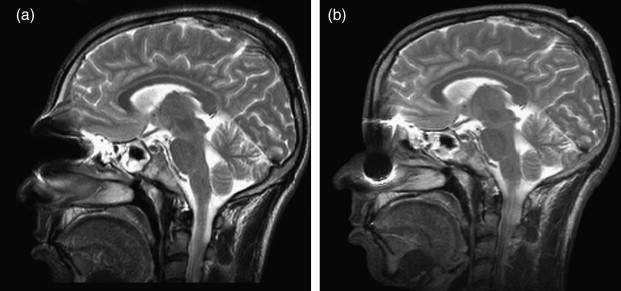

(7) 為什麼不照相或錄影 ??? 再想想, 金剛換體禪並不是開"心", 而是開"頂". 頭頂有沒有打開, 這些法師法王都是光頭或小平頭, 讓人瞧一眼就知道了, 用手機照張相片或錄影就知道了, 何必大費周章, 一群華藏寺法師法王都跑到醫院去照昂貴的MRI呢 ?! 直接證據不用, 卻要用可容造假的間接證據.

因為照MRI可以拿來欺騙唬弄不知內情的的信徒與善男信女 !

(9)"老闆娘, 我也要來一張!"在台灣的健保, 病況需要時每半年可以免費照一張MRI. 所以只要在頭頂上噴灑一些金屬粉末, 並用髮膠固定. 細小的黑粉末是一定可以讓現場醫事檢驗人員既看不出來也摸不出來, 如此就可瞞過醫院. 去看醫生時就說頭內部很不舒服. 要求要照MRI. 公立醫院通常比較不會輕易讓病人照MRI. 少數私立醫院因為購買MRI機器的成本非常昂貴, 因此比較可能會照MRI, 目的顯然是為了回本.

就這樣, 你幾乎不花一毛錢, 就可以輕易瞞天過海又免費照出並拿到"開頂成聖"的MRI影像圖了. 先讓台灣健保替你付費. 如果你要, 還可在公車火車坦克車上打廣告, 再讓台灣信徒把你當大聖德大法王敬拜供養.